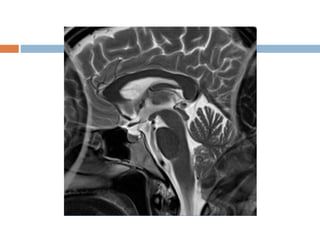

Slice overlapping

 Loss of signal due to multi slice, multi angle

acquisition or imperfect slice profile.

 Mechanism : Spin saturation.

 If slices at different angles cross, then spins that

have previously excited, could be excited again.

 Mostly seen in spine imaging e.g. L4-L5 or L5-

S1.

 Appearance

 Band of signal loss crossing horizontally in the

image, usually posteriorly.

 Solution

 Continuous imaging

 Increase slice gap.

Slice overlapping  Lossof signal due to multi slice, multi angle acquisition or imperfect slice profile.  Mechanism : Spin saturation.  If slices at different angles cross, then spins that have previously excited, could be excited again.  Mostly seen in spine imaging e.g. L4-L5 or L5- S1.

 Appearance  Bandof signal loss crossing horizontally in the image, usually posteriorly.  Solution  Continuous imaging  Increase slice gap.